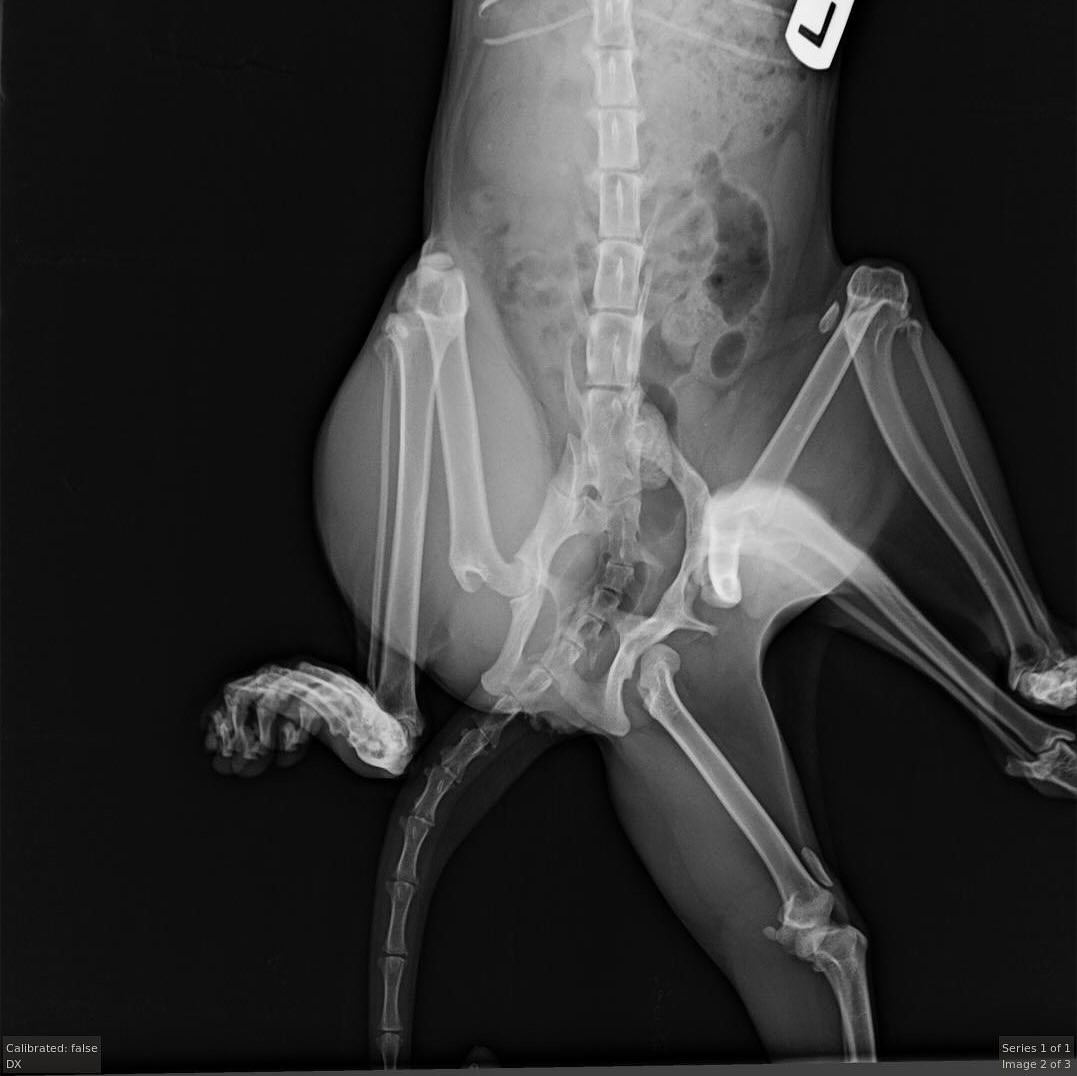

Veterinári v Kanade zostali v šoku, keď na ich kliniku prišla túlavá mačka so šiestimi nohami. Zistili, že ďalší pár končatín jej vyrastal zo zadnej časti tela. Ako informoval portál Daily Mail, domnievajú sa, že mačka mala nohy navyše od dvojčaťa, ktoré absorbovala počas vývoja v maternici.

Veterinári sa domnievajú, že Bitsy mala mať dvojča, no počas vývoja v maternici ho absorbovala. To spôsobilo, že sa mačke vytvorili až štyri zadné končatiny. Bohužiaľ, tri z nich boli nefunkčné, čo Bitsy spôsobovalo nepohodlie a obmedzovalo jej pohyblivosť. "Jednoduché úkony, ako napríklad polohovanie, boli pre ňu náročné," vysvetlila Koltun.